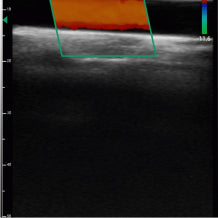

Real life images

Our devices reproduce excellent image quality.